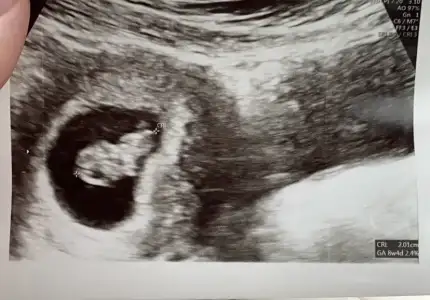

Yani bu sekildeyse erkek mi oluyor bu karın ultutasonu fotosu düz mü sayılıyo tersmi ben anlamadım bunu 9 haftalıkken almıştık bu görüntüyü😍

Benim ilk öğrenmeye gittiğim vakit yani yaklasik 6 haftalık iken sağ yerleşimliydi.Sizin ki de sağa yakın gibi ama 9 haftada ramzi teorisi turuyor mu bilmiyorum :) :)

Valla bende aslnda cin takvimi kız diyo içimdende Allahın zoruna gitmesin hep kız geçiyo rüyamdada pembe balonlar görmüstüm artık hayırlısı sağlıkla gelsinde 😍ben düz sandım bu görüntüyü sola yakın sanıyorum😂😂😂

Benim bebek 6.hafta ilk ultrasonda soldaydı 8. Haftada sağa dönmüştü. Değişiyor bence ilk tutunduğu yer önemli diye biliyorum ramzide.

6. Haftadan sonra bebiş ortalara doğru kayıyo, ben de ramziyi 6. Haftaya kadar doğru diye biliyorum:)